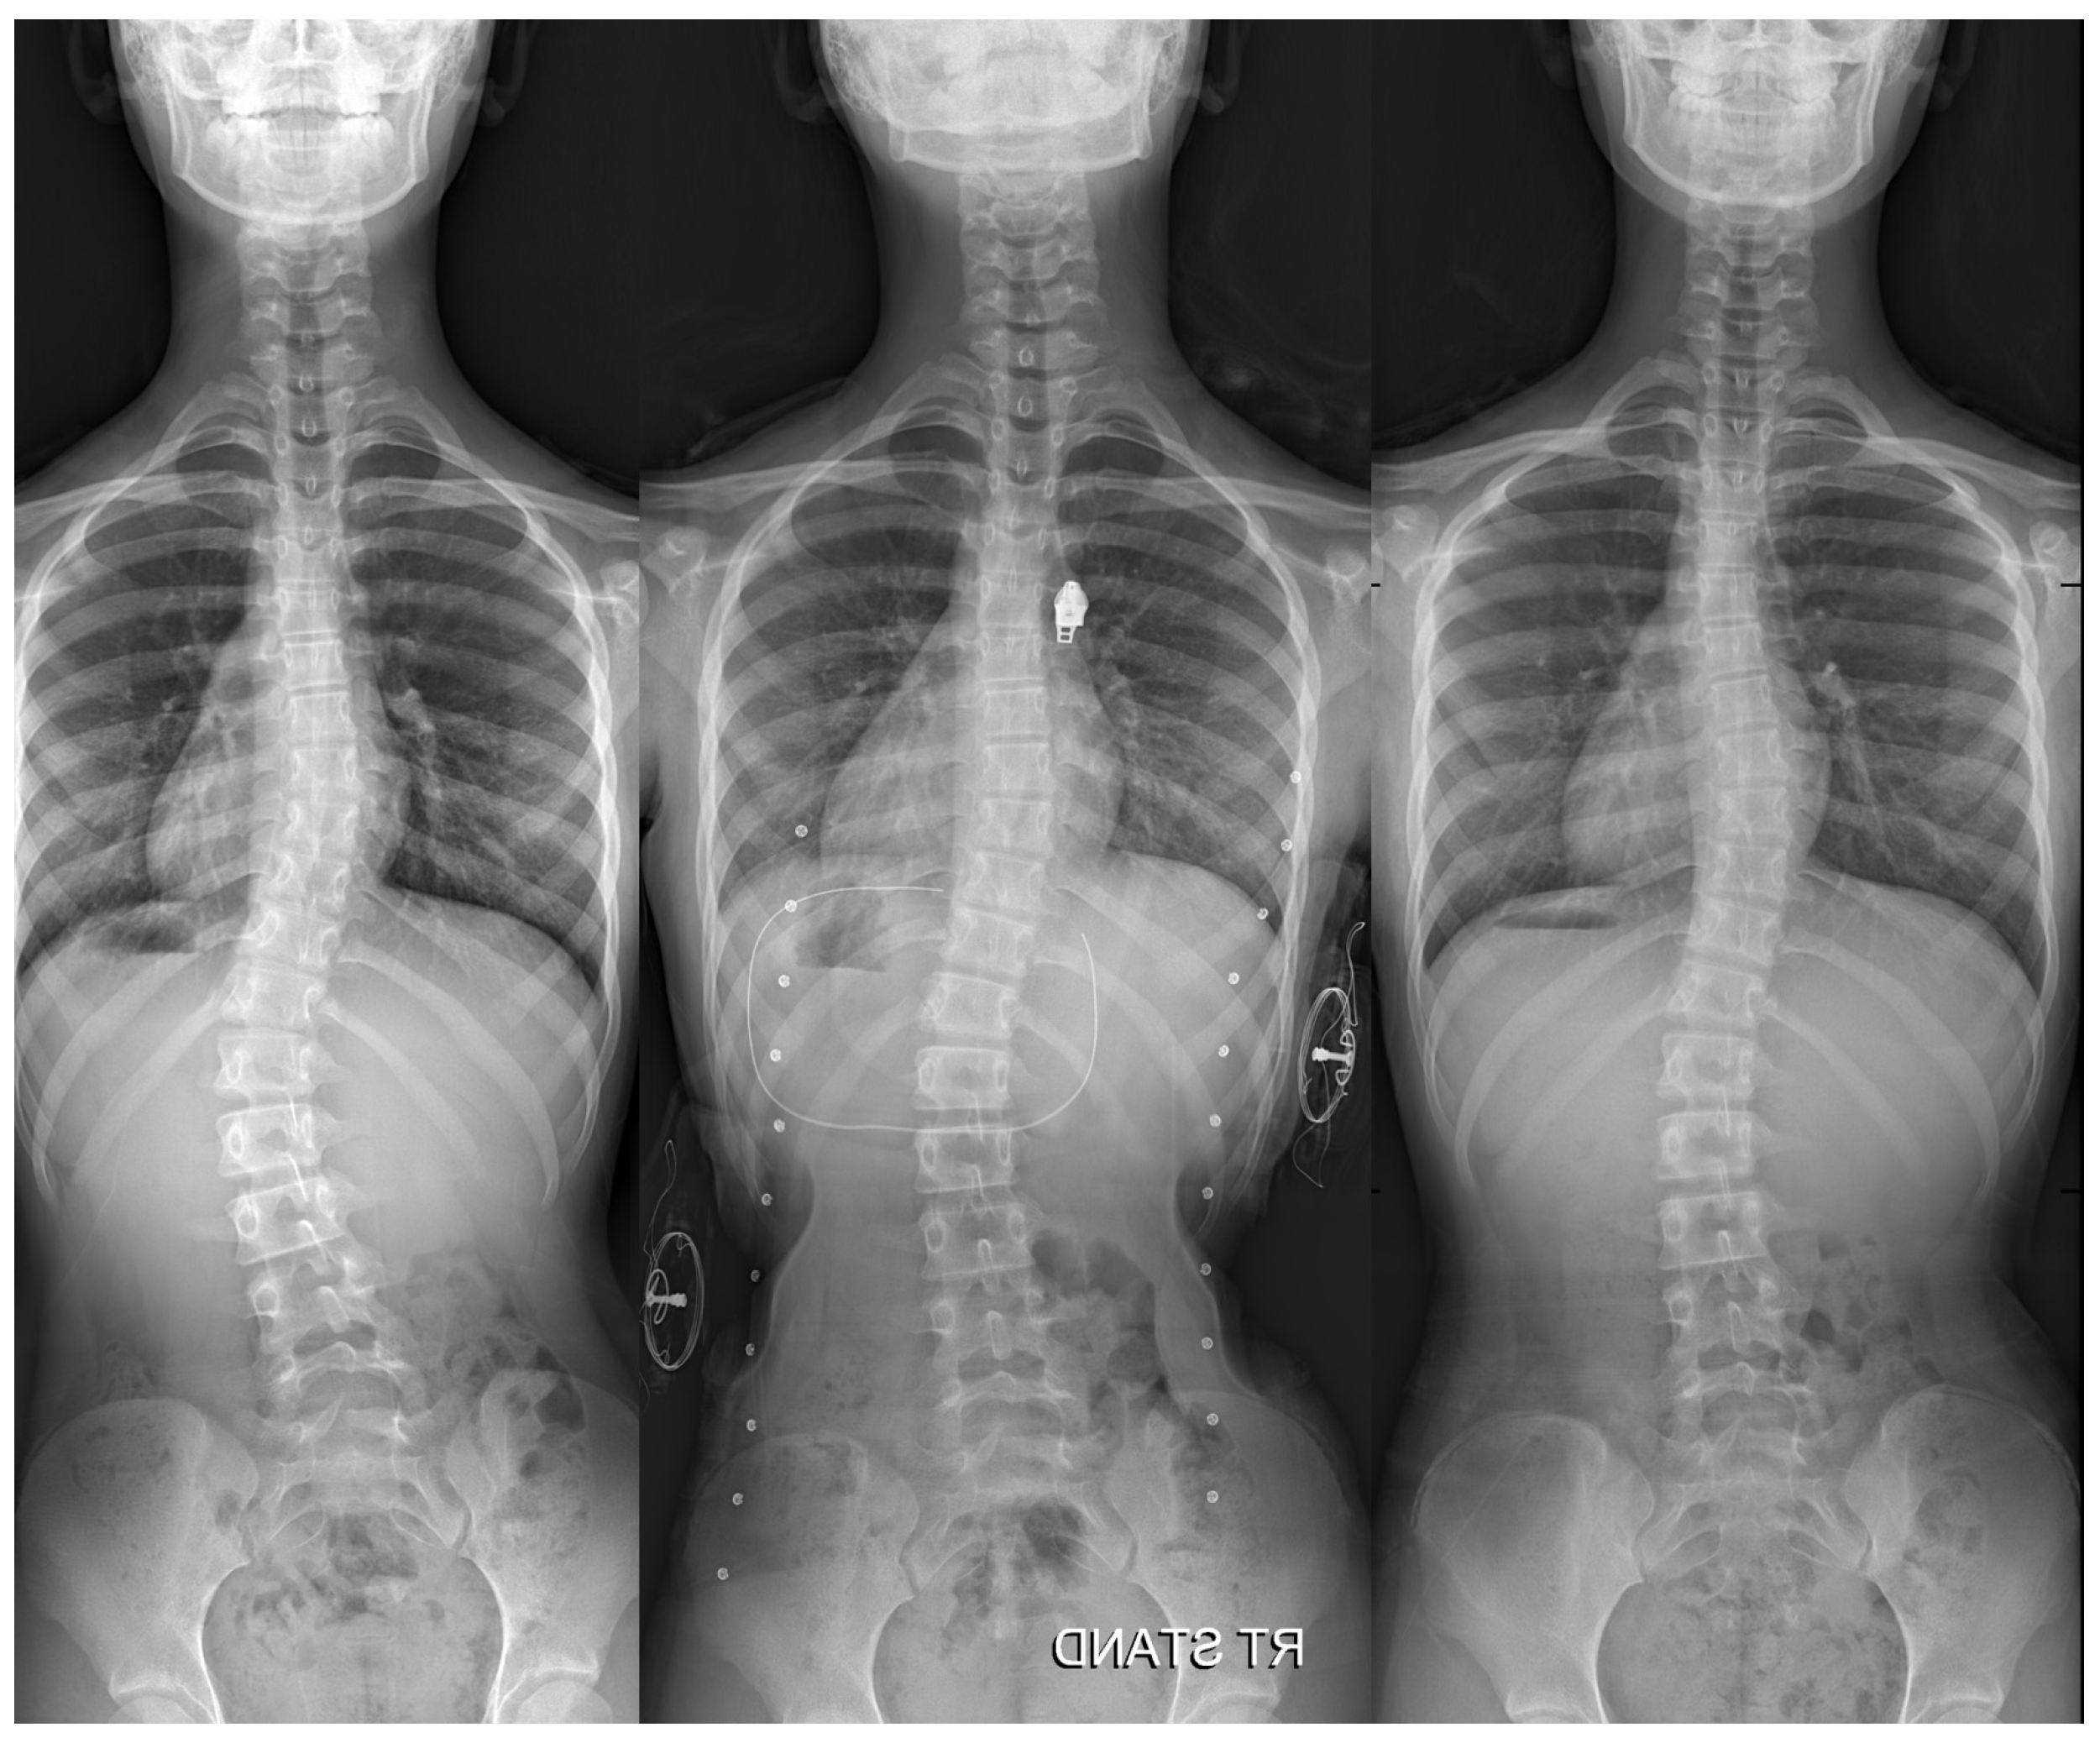

The Efficacy of a Novel Hybrid Brace in the Treatment of Adolescent Idiopathic Scoliosis: A Prospective Case-Series Study

2.2. Hybrid Brace Treatment and Follow-Up